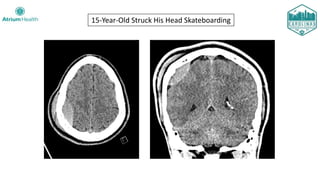

15-Year-Old Struck His Head Skateboarding

Case #2

15-year-old male brought into the ED by his parents after un-helmeted fall

off skateboard.

Clinical Course:

• Taken to Operating Room with neurosurgery for craniotomy

• Uncomplicated post-operative course

• Discharged on post-operative Day #3 with a prescription for levetiracetam

• Seen by pediatric neurology at 1.5 months, no further seizures

• Plan for discontinuation of antiepileptics if a 6-month EEG is negative

• Unfortunately, the patient was lost to follow up